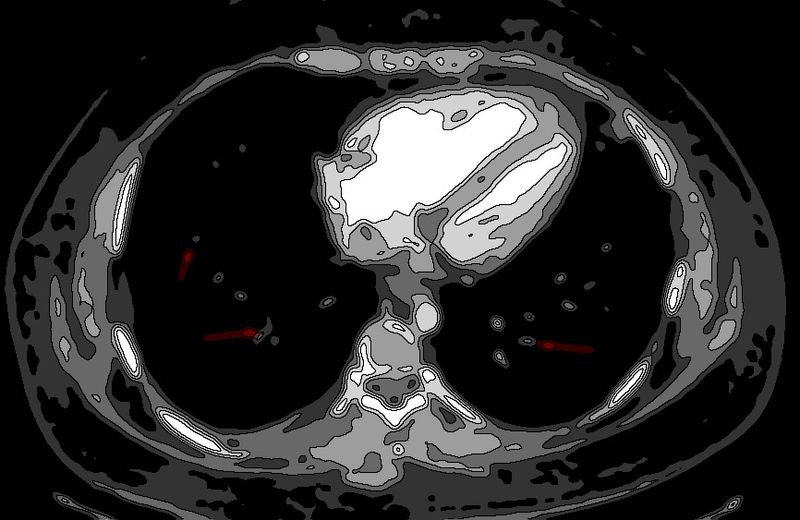

Эндокардит и сепсис у 34-летнего наркозависимого мужчины

Эндокардит и сепсис у 34-летнего наркозависимого мужчины